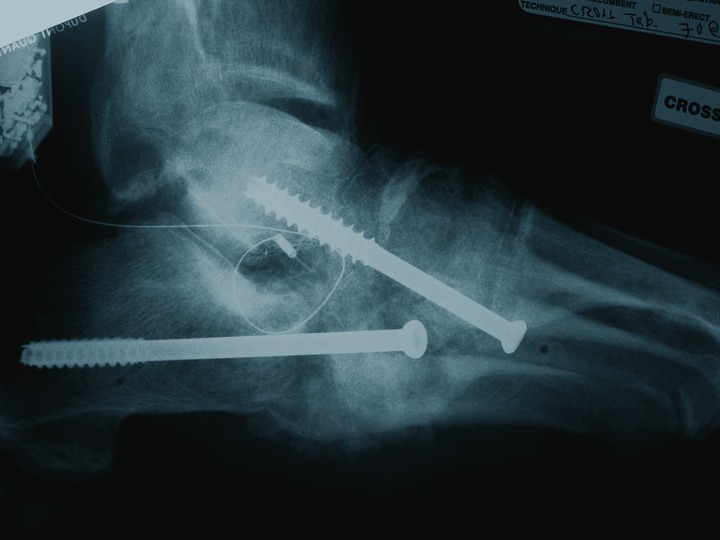

As one can see in the above photo, the arthrodesis interface biologics include an implantable bone stimulator, fresh frozen femoral head allograft and demineralized bone matrix (DBM).

The above photo shows a one-week post-op radiograph with external fixation.